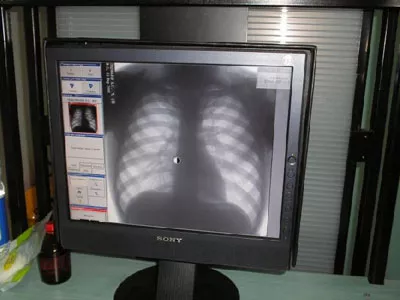

Регулярное флюорографическое обследование — надежная профилактика туберкулеза

Флюорография для взрослых и подростков, проведение туберкулинодиагностики у детей (реакция Манту) — это основные и самые доступные для всех методы ранней диагностики туберкулеза, что также является профилактикой, поскольку в случае выявления болезни прерывается «цепочка» распространения инфекции. Стремимся к 100-процентному обследованию групп риска, декретированного контингента (медики, педагоги, работники торговли, пищевики и т.д.) и лиц, не обследовавшихся 2 года и более (именно в этой группе выявляемость туберкулеза в три раза выше, чем среди остальных). Продолжаем работу с правоохранительными органами по привлечению туберкулезных больных, уклоняющихся от обследования и лечения.